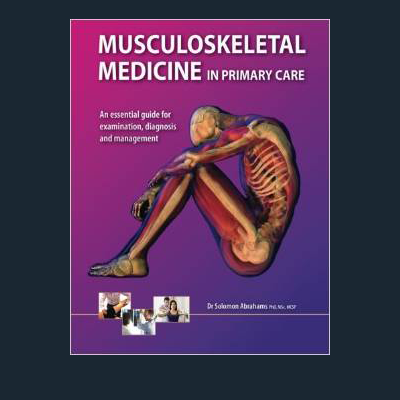

Solomon is one of a few UK Physiotherapists with a PhD Doctorate and has published a number of clinical articles on Musculoskeletal and Orthopaedic Medicine in scientific journals. He has also published two clinical text books, one of which is a best seller in the US. One book is dedicated to Children & Adolescent Sports Injuries and the other book is on Adult Sport Injuries.

He has also taught at the Masters in Physiotherapy at the prestigious Kings College University London and Cambridge Universities. He has taught at various Doctors and GP’s in different health authorities within the London area and has a consultant role for the NHS within care commissioning groups. His text book Musculoskeletal Medicine in Primary Care: An Essential Guide for Examination, Diagnosis and Management is freuently used by students and professionals alike. It is also available at Amazon.